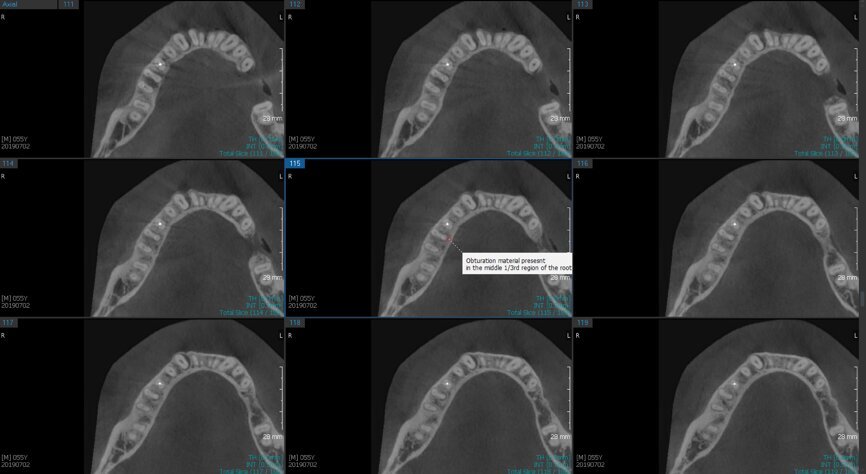

Fig.2a: Pre-op CBCT images of tooth #46: No obturation material in the distal and mesiobuccal canal (a); scanty obturation of the canals and breach of the floor of the pulp chamber, no obturation beyond a few millimetres down the orifice (b & c); radiolucency in the furcation area and periapical region of both roots (d -g).

Fig.2b: Pre-op CBCT images of tooth #46: No obturation material in the distal and mesiobuccal canal (a); scanty obturation of the canals and breach of the floor of the pulp chamber, no obturation beyond a few millimetres down the orifice (b & c); radiolucency in the furcation area and periapical region of both roots (d -g).

Fig.2c: Pre-op CBCT images of tooth #46: No obturation material in the distal and mesiobuccal canal (a); scanty obturation of the canals and breach of the floor of the pulp chamber, no obturation beyond a few millimetres down the orifice (b & c); radiolucency in the furcation area and periapical region of both roots (d -g).

Fig.2d: Pre-op CBCT images of tooth #46: No obturation material in the distal and mesiobuccal canal (a); scanty obturation of the canals and breach of the floor of the pulp chamber, no obturation beyond a few millimetres down the orifice (b & c); radiolucency in the furcation area and periapical region of both roots (d -g).

Fig.2e: Pre-op CBCT images of tooth #46: No obturation material in the distal and mesiobuccal canal (a); scanty obturation of the canals and breach of the floor of the pulp chamber, no obturation beyond a few millimetres down the orifice (b & c); radiolucency in the furcation area and periapical region of both roots (d -g).

Fig.2f: Pre-op CBCT images of tooth #46: No obturation material in the distal and mesiobuccal canal (a); scanty obturation of the canals and breach of the floor of the pulp chamber, no obturation beyond a few millimetres down the orifice (b & c); radiolucency in the furcation area and periapical region of both roots (d -g).

Fig.2g: Pre-op CBCT images of tooth #46: No obturation material in the distal and mesiobuccal canal (a); scanty obturation of the canals and breach of the floor of the pulp chamber, no obturation beyond a few millimetres down the orifice (b & c); radiolucency in the furcation area and periapical region of both roots (d -g).

When I had a close look at the preoperative radiograph from the referring dentist (Fig. 1a), I observed that there was insufficient obturation of the mesial canals and almost no obturation of the distal canal. Both roots displayed periapical radiolucency. The clinical examination revealed a Grade I mobility, and the tooth was tender to percussion. The periodontal examination ruled out any pockets and loss of attachment. We took an intra-oral periapical radiograph (Fig. 1b), from which we observed the loss of coronal structure and a large radiolucent area over the furcation area and the periapical area of both the mesial and the distal roots. A CBCT scan of tooth #46 was advised to check for any details that may have been missed in the intra-oral periapical radiograph (Figs. 2a–g). From the CBCT scan, it could be observed that there was inadequate obturation of the distal canal on the horizontal plane, no obturation beyond the middle third in the mesial canals and a breach of the floor of the pulp chamber. The questionable prognosis was explainedto the patient, and written consent was obtained.